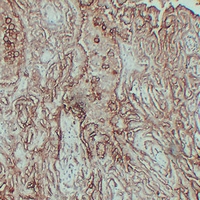

IHC (Immunohistochemistry)

(Immunohistochemical analysis of MUC16 staining in human mesothelioma formalin fixed paraffin embedded tissue section. The section was pre-treated using heat mediated antigen retrieval with sodium citrate buffer (pH 6.0). The section was then incubated with the antibody at room temperature and detected using an HRP conjugated compact polymer system. DAB was used as the chromogen. The section was then counterstained with haematoxylin and mounted with DPX.)